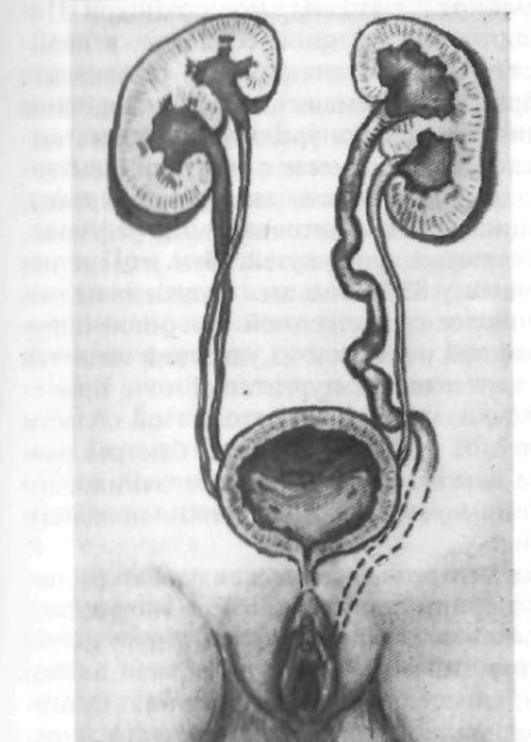

Рефлюксирующий мегауретер: Визуализация и медицинские изображения

Раздел: Фотопуть к знанию